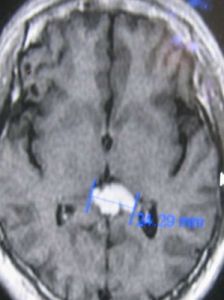

松果體是約7×4mm2大小的扁錐形小體,位於丘腦後上方,以柄附於第三腦室頂的後部。松果體在兒童時期較發達,一般7歲後逐漸萎縮,成年後不斷有鈣鹽沉著。